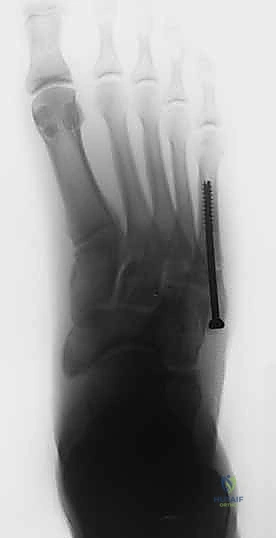

الدليل الجراحي الشامل: عملية التثبيت بالمسمار النخاعي الداخلي

عملية تثبيت كسر جونز بالمسمار النخاعي (Intramedullary Screw Fixation) هي جراحة دقيقة تتطلب مهارة استثنائية. وهي من التخصصات الدقيقة التي يتميز بها الأستاذ الدكتور محمد هطيف في صنعاء.

خطوات العملية الجراحية (خطوة بخطوة)

- الشق الجراحي الدقيق (Minimally Invasive): لا يقوم الدكتور هطيف بفتح شق كبير، بل يُحدث شقاً صغيراً جداً (حوالي 1 إلى 2 سم) عند قاعدة العظمة الخامسة لمشط القدم. هذا الشق الصغير يقلل من الألم بعد العملية ويسرع التئام الجرح ويحافظ على الشكل الجمالي للقدم.

- إدخال سلك التوجيه (Guide Wire): تحت توجيه الأشعة السينية المباشرة في غرفة العمليات، يتم إدخال سلك معدني رفيع جداً ليمر عبر الكسر وصولاً إلى النخاع العظمي. هذه الخطوة تتطلب دقة متناهية لضمان أن السلك في المنتصف تماماً.

- التحضير والتوسيع (Drilling/Tapping): يتم استخدام مثقاب خاص مجوف يمر فوق سلك التوجيه لتوسيع القناة النخاعية وتجهيزها لاستقبال المسمار.

- إدخال المسمار التيتانيوم (Screw Insertion): يتم اختيار مسمار طبي من التيتانيوم (طوله وسمكه محسوبان بدقة لتناسب عظمة المريض). يتم إدخال المسمار ليربط بين جزئي الكسر، مما يولد قوة ضغط (Compression) تجعل حواف العظم متلاصقة تماماً، وهو السر وراء الالتئام السريع.

- الإغلاق التجميلي: يتم إغلاق الشق الصغير بغرز تجميلية، ووضع ضمادة معقمة وحذاء طبي لحماية القدم.